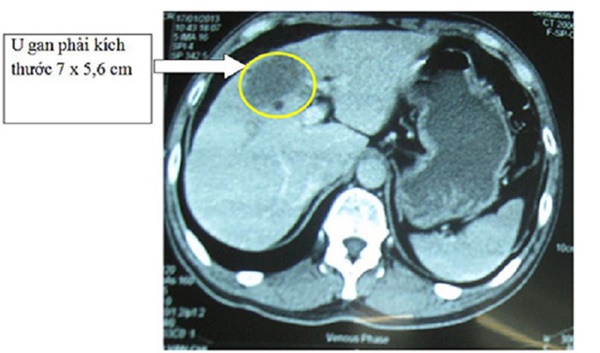

Hình ảnh u gan.